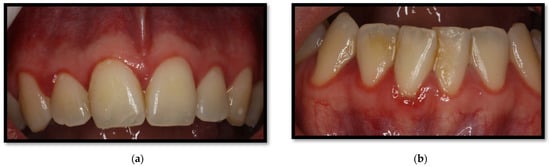

3.1. Linear Gingival Erythema